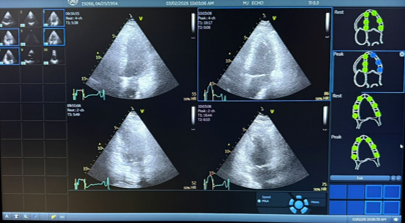

Ultrasound images are obtained before and immediately after exercise.

The test typically takes about 20-30 minutes. You will be closely monitored during exercise, and ultrasound images will be obtained before and immediately after the treadmill portion. There is no radiation involved.

Stress echocardiogram images help evaluate blood flow to the heart muscle.